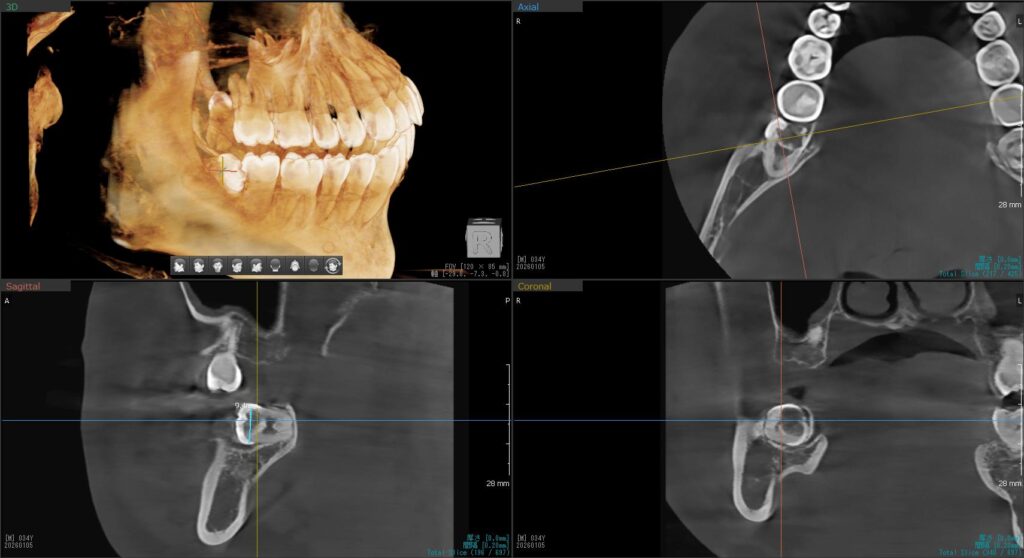

そして4番目の患者様。

年明けに予定していた右上の親知らずの抜歯を行いました。

CTで確認すると、上顎洞に近いため「上顎洞炎」になる可能性がある、難症例です。

事前にお薬を飲んでいだたいていよいよ抜歯開始です。

親知らずは完全に歯茎の中に埋まっている状態のため、まずは歯茎を切開。

親知らずの周りの骨を最小限削っていき、抜いていくスペースを作ります。

そこから親知らずを掴んで慎重に抜いていき、抜歯完了です!